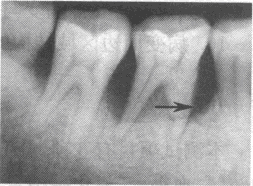

指出右图的病变类型

A、牙槽骨吸收Ⅱ度

B、牙槽骨吸收Ⅲ度

C、牙槽骨水平吸收

D、牙槽骨垂直吸收